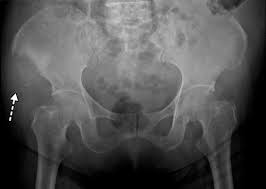

} myeloma cells produce paraproteins which are found in blood and urine (protein bence jones). The pelvis contains numerous lytic lesions without reactive sclerosis which have multiple myeloma. Healthy plasma cells help you fight infections by making antibodies that recognize and attack germs. Spotlight revised international staging system for multiple myeloma: Multiple myeloma is a cancer of plasma cells, which are white blood cells found mainly in the bone marrow. If you still can't find it, please let us know so we can add it!. Other tests include blood monoclonal immunoglobulin and radiology tests to determine the extent of bone lesions. Multiple myeloma is the second most common type of blood cancer after leukemia. 1,2,3 it accounts for approximately 1% of all malignant. Treatment response, detection of relapse. International myeloma working group molecular classification of multiple myeloma: It accounts for approximately 10% of all. Extraosseous myeloma refers to any manifestation of multiple myeloma where there is plasma cell proliferation outside the atypical manifestations of multiple myeloma: